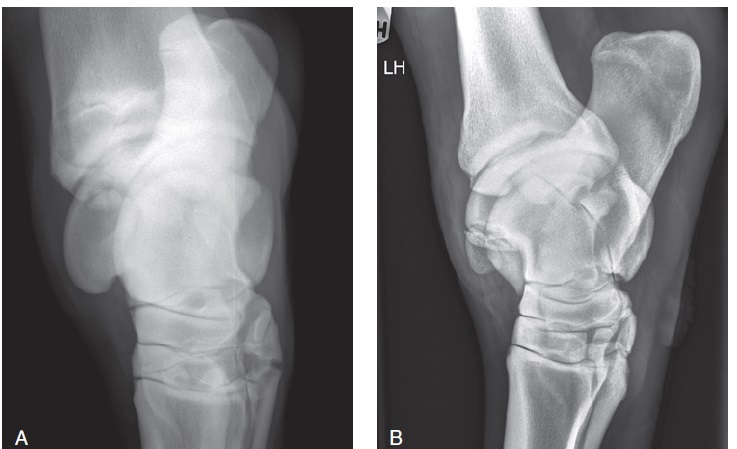

Figure 99-29. Arthroscopic view of the lateral trochlear ridge OCD lesion before (A) and after (B) removal of the large osteochondral fragment (see radiographic view in Figure 99-24, B). The DMPLO radiographic view shows the successful removal of the fragment (C).